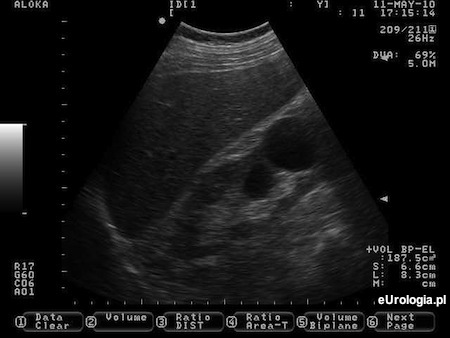

Ultrasonografia jamy brzusznej jest najczęstszym badaniem obrazowym, podczas którego stwierdzana jest torbiel nerki. Według Daltona torbiel nerki musi spełniać następujące kryteria aby móc rozpoznać torbiel prostą nerki :

bezechowa zawartość

kulisty lub owalny kształt

dobrze widoczna ściana dystalna

wzmocnienie echa poza torbielą

Fot. Torbiel prosta prawej nerki widoczna w USG.